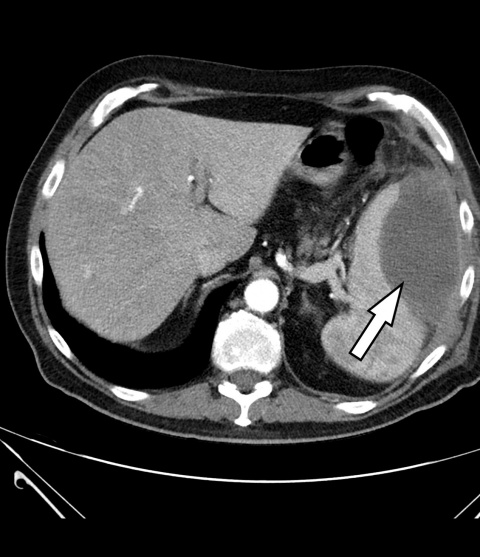

CT